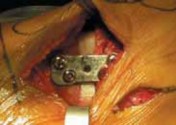

PLATE FIXATION

1. The handle of the osteotomy wedge can be removed (

TECH FIG 5A

), leaving the anterior and posterior tines in place.

1. The proper-sized osteotomy plate is then inserted into the osteotomy site (

TECH FIG 5B

). To respect the geometry of the tibial slope, it is recommended that the wedge in the plate be sloped from posterior to anterior.

2. The use of second-generation locking plates is recommended.

3. Before fixation of the plate, the tines are removed from the osteotomy wedge (

TECH FIG 5C

).

2. The plate is secured with two 6.5-mm fully threaded cancellous screws in the proximal fragment. (It is not necessary to use bicortical screws.) The distal fragment is secured with two 4.5-mm bicortical screws.

TECH FIG 5 • A. The handle of the osteotomy wedge is removed, and the wedge trial is placed between the tines to confirm the size of the osteotomy plate to be used.

TECHNIQUES TECH FIG 5 •

(continued)

B. The osteotomy plate is trialed. In this case, the posterior tine is in place and the anterior tine has been removed. C. Second-gener-ation locking plate in place. The white arrow points to the mark on the plate verifying the slope from anterior to posterior (ie, the trapezoid is larger posterior B C than anterior). BONE GRAFTING 1. Depending on the preference of the surgeon and patient, the osteotomy must be packed with bone graft and the medial cortical margins reinforced with tricortical iliac crest graft.